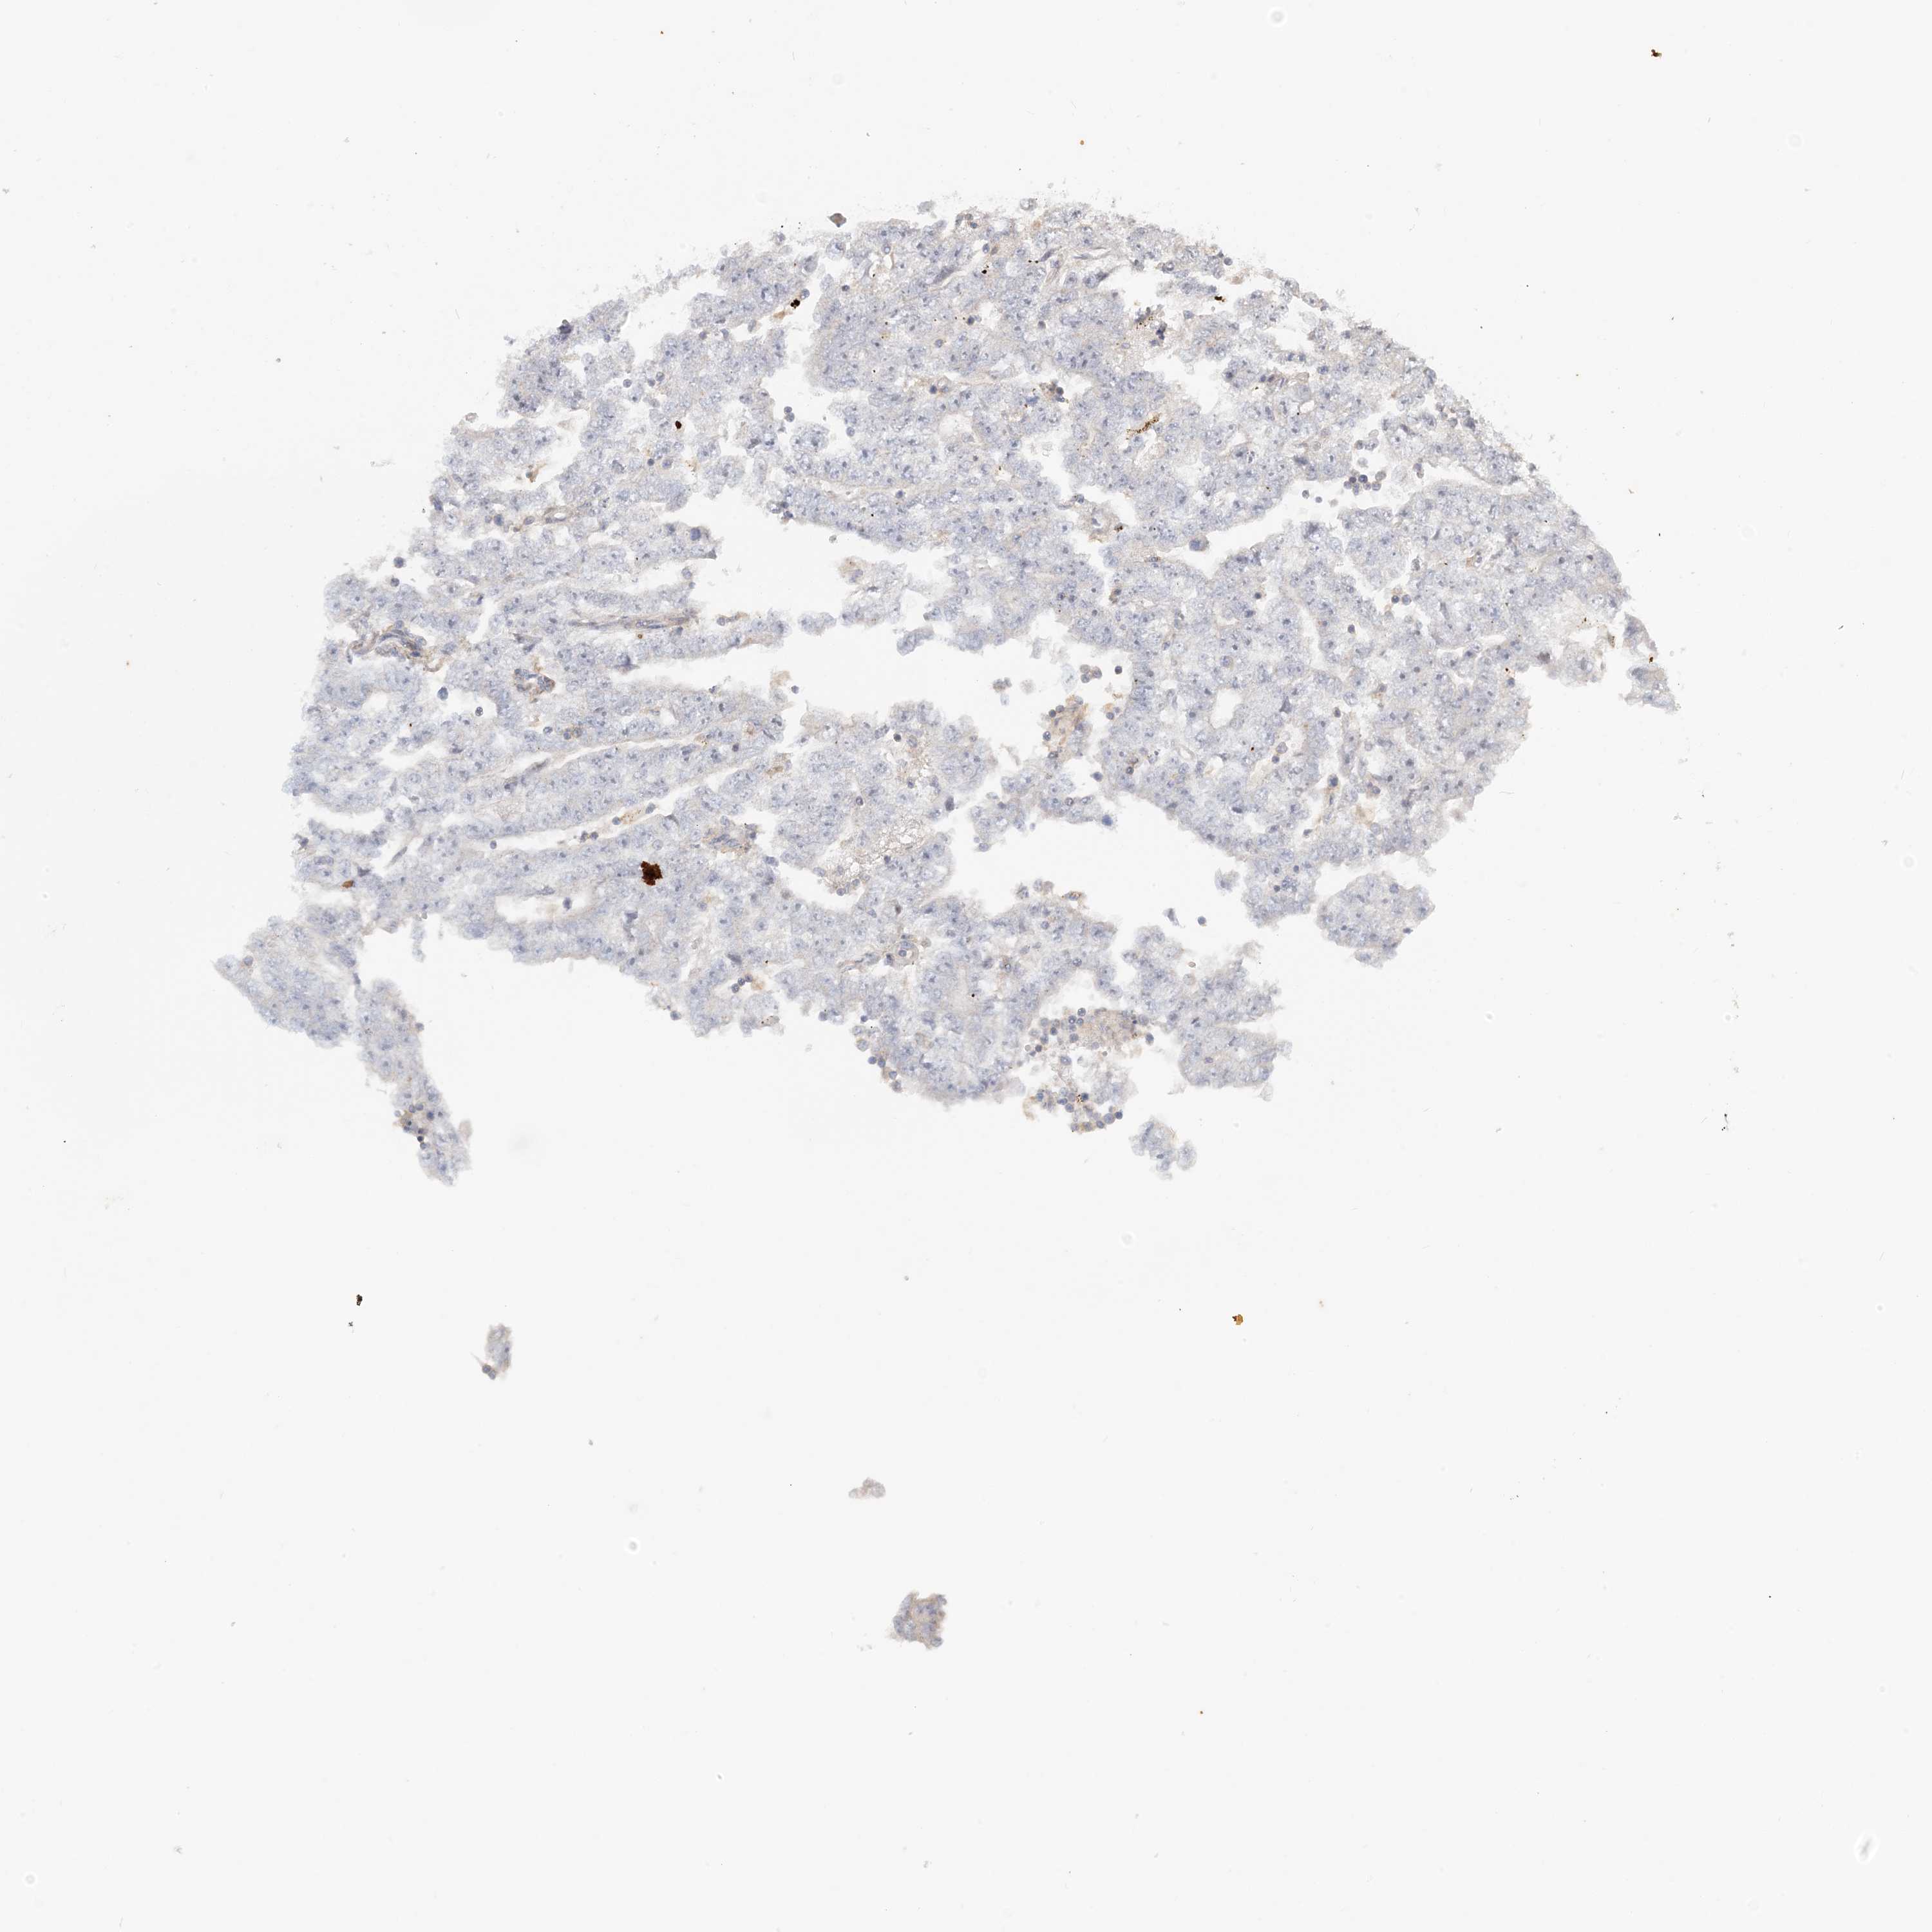

TESTIS CANCER - Protein expressioni

A mouse-over function shows sample information and annotation data. Click on an image to view it in a full screen mode. Samples can be filtered based on level of antibody staining by selecting one or several of the following categories: high, medium, low and not detected. The assay and annotation is described here.

Note that samples used for immunohistochemistry by the Human Protein Atlas do not correspond to samples in the TCGA dataset.

Antibody stainingi

Antibody staining in the annotated cell types in the current human tissue is reported as not detected, low, medium, or high, based on conventional immunohistochemistry profiling in selected tissues. This score is based on the combination of the staining intensity and fraction of stained cells.

Each image is clickable and will lead to virtual microscopy that enables deeper exploration of all samples and also displays staining intensity scores, fraction scores and subcellular localization as well as patient and tissue information for each sample.

Antibody HPA035241

Carcinoma, Embryonal, NOS

Seminoma, NOS

Urothelial carcinoma, High grade